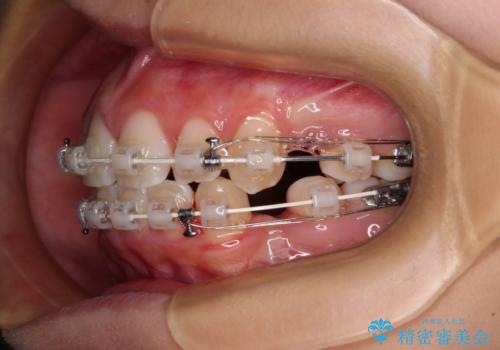

気がつくと唇があいてしまう ワイヤー装置での抜歯矯正

- 口元の突出感で口が閉じにくいとのことで来院された患者様です。

上下左右の第一小臼歯4本を抜歯し、ワイヤー装置での抜歯矯正を行うこととしました。

右側の咬み合わせは、上顎がやや前方位にある状態であったので、通常は補助装置を併用するのですが、高校生ということで補助装置なしで治療を行うこととしました。

- 審美装置

- 2年2ヶ月